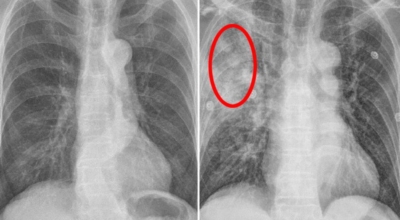

건강한 폐를 위해서는 폐의 활동을 유지하는데 도움을 주는 건강에 좋은 음식을 섭취해야 합니다. 폐는 우리 몸에서 중요한 역할을 하는 것은 말할 필요도 없어요. 그러나 결국 폐는 공기 뿐만 아니라 대기 오염과 담배 연기 같은 유해한 요소를 흡입하게 되는데요. 이런 오염 물질은 천식, 기관지염, 낭포성 섬유증 또는 폐렴등의 호흡기 건강 문제의 위험을 증가시켜요.

세계보건기구인 WHO 에 의하면 2억 3천5백만 명이 천식으로 고통 받고 있으며 이는 진단 또는 치료가 부족한 상태이지요. 그렇기 때문에 폐 건강을 향상시키기 위해서는 폐에 좋은 음식을 섭취할 필요가 있어요.